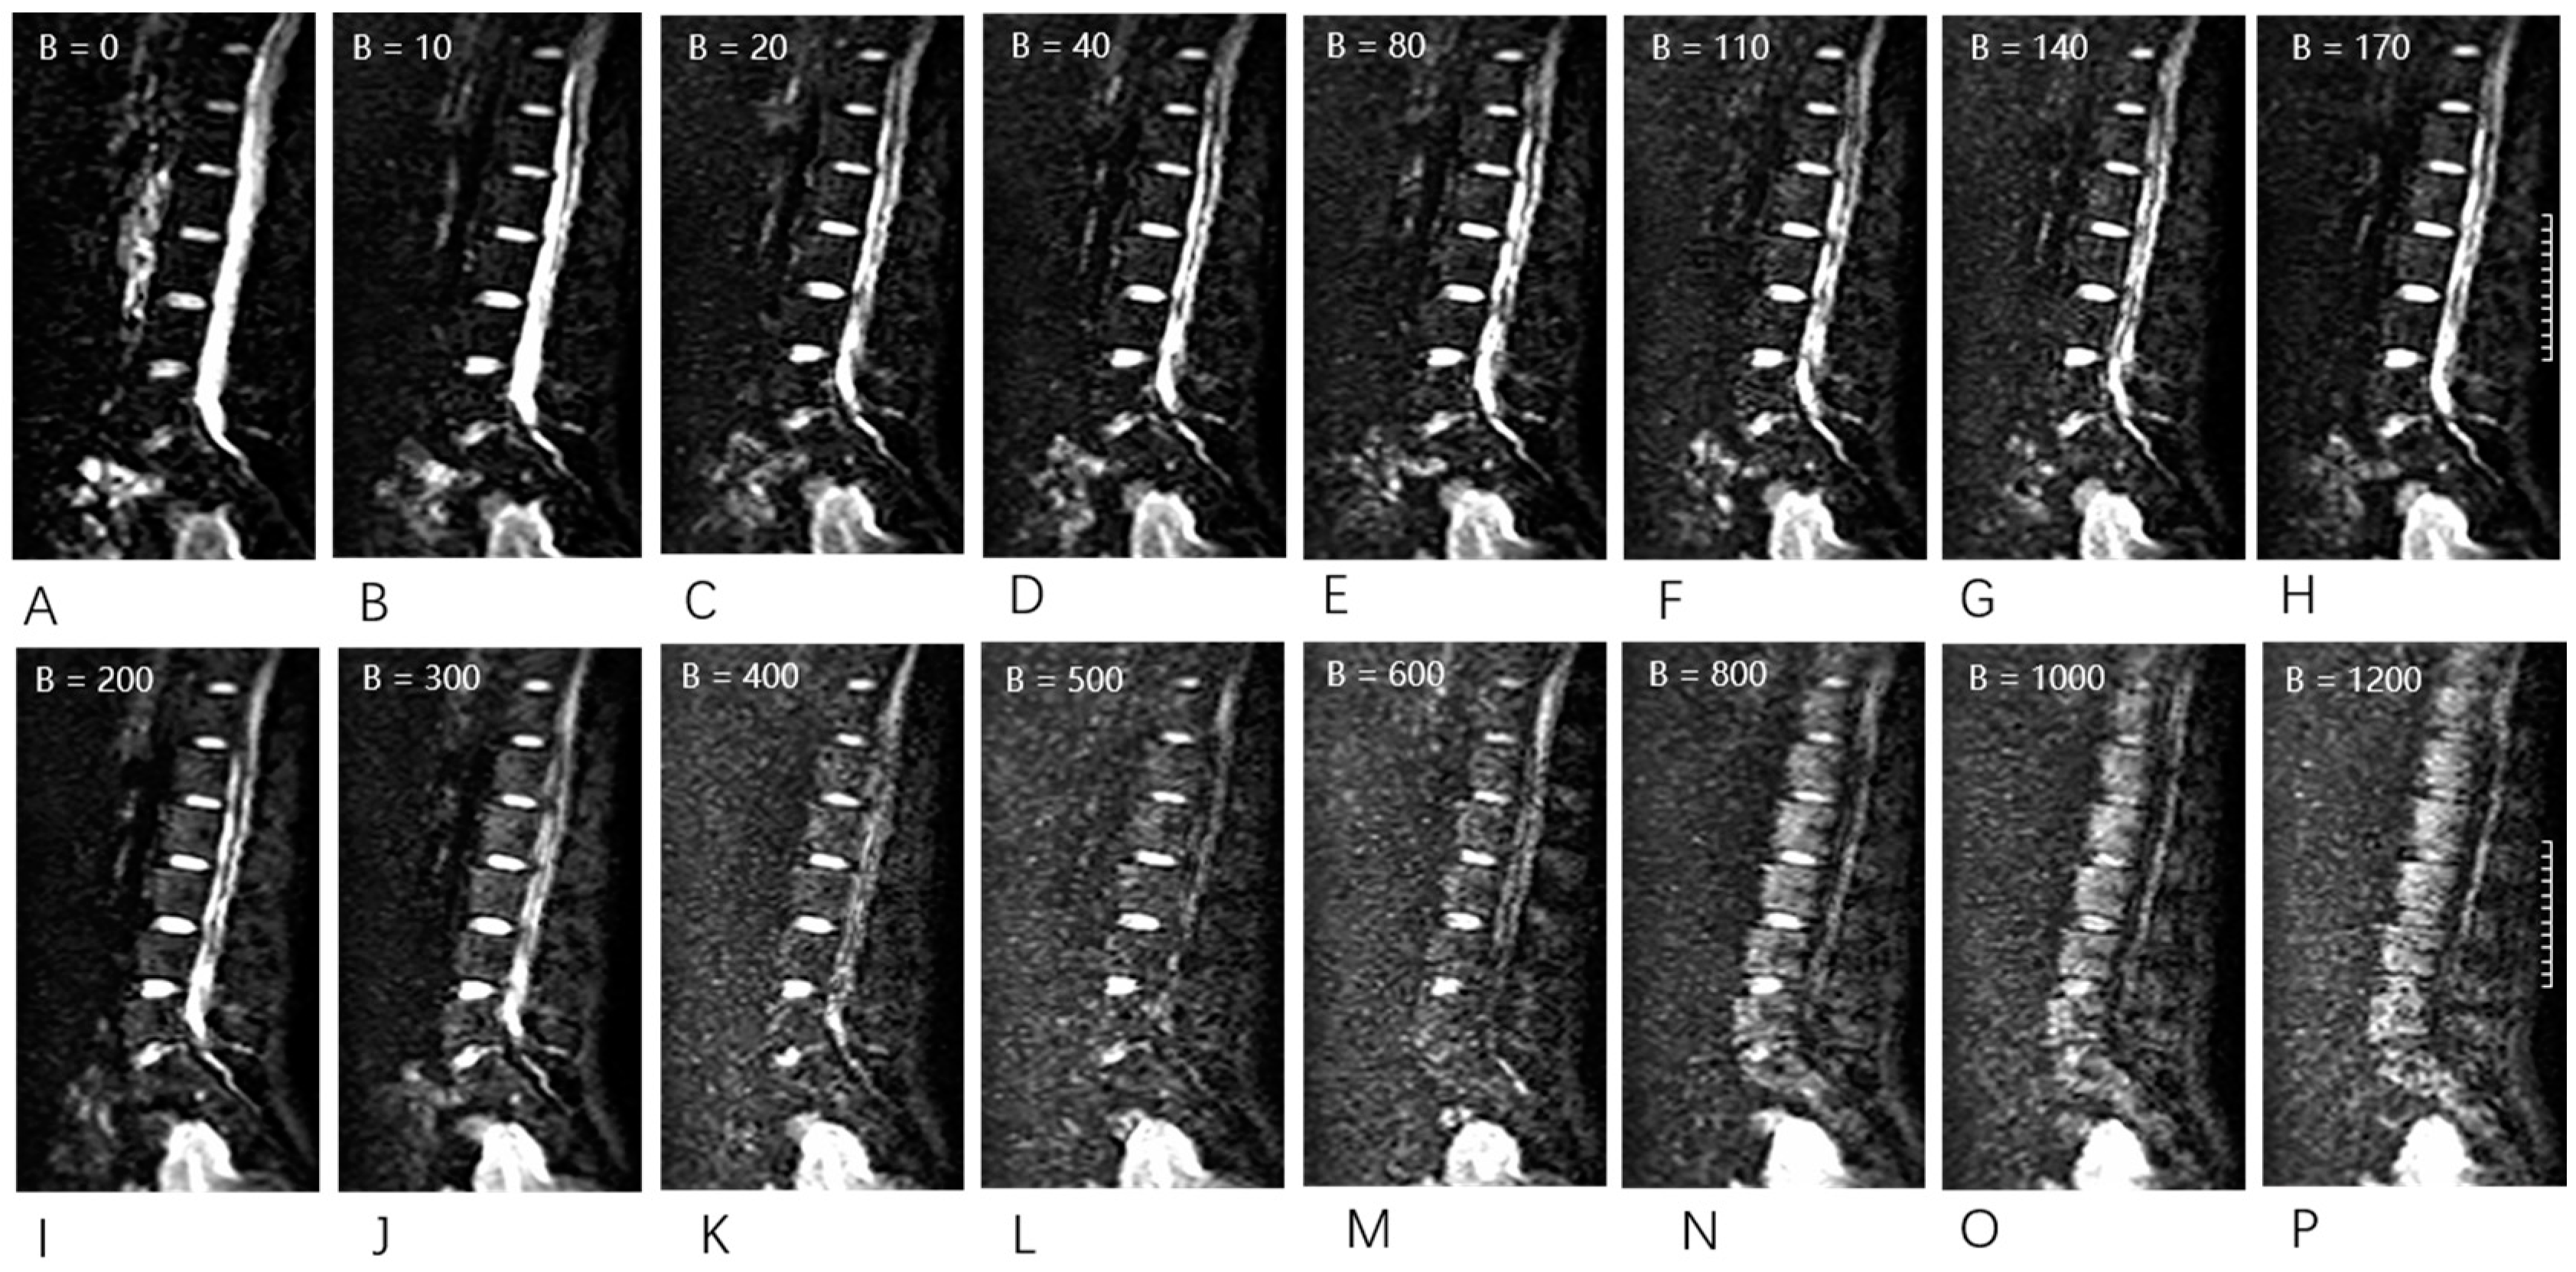

2.4. MR Examination

2.5. Image Analysis